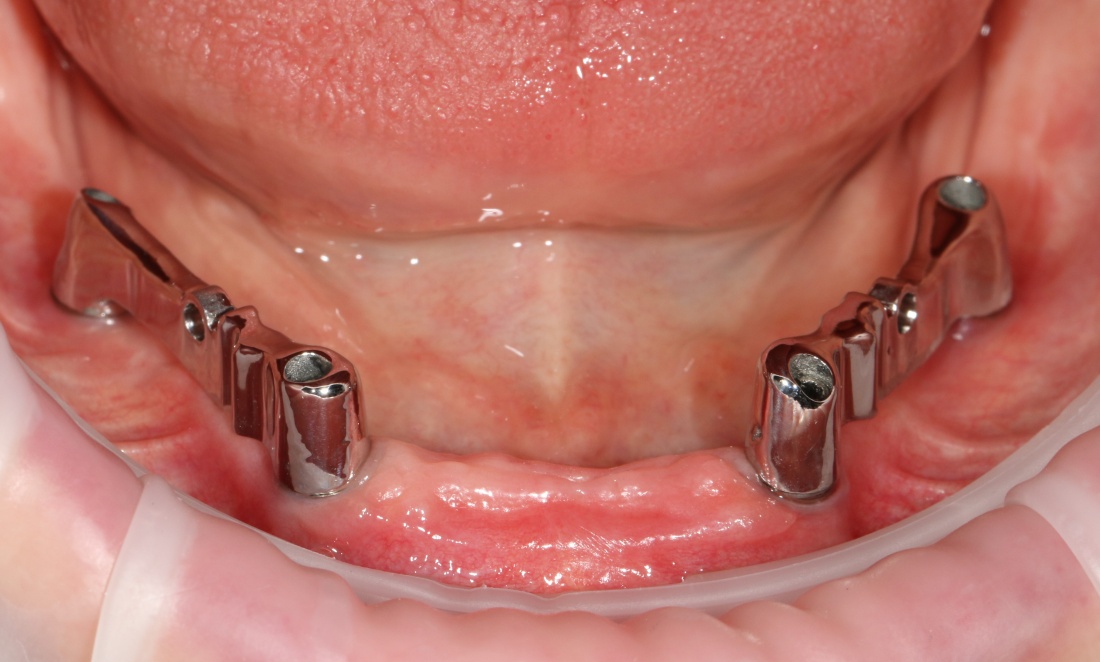

Самый простой пример — это хронический пародонтит, в условиях которого немедленная имплантация представляет определённые риски с точки зрения сохранения окружающих имплантат тканей:

Именно поэтому к широко рекламируемым методам «всё-на-четырёх» или All-On-4 нужно относиться крайне осторожно — иногда лучше решать такие клинические задачи не быстро и за один раз, а в несколько этапов, последовательно и безопасно.